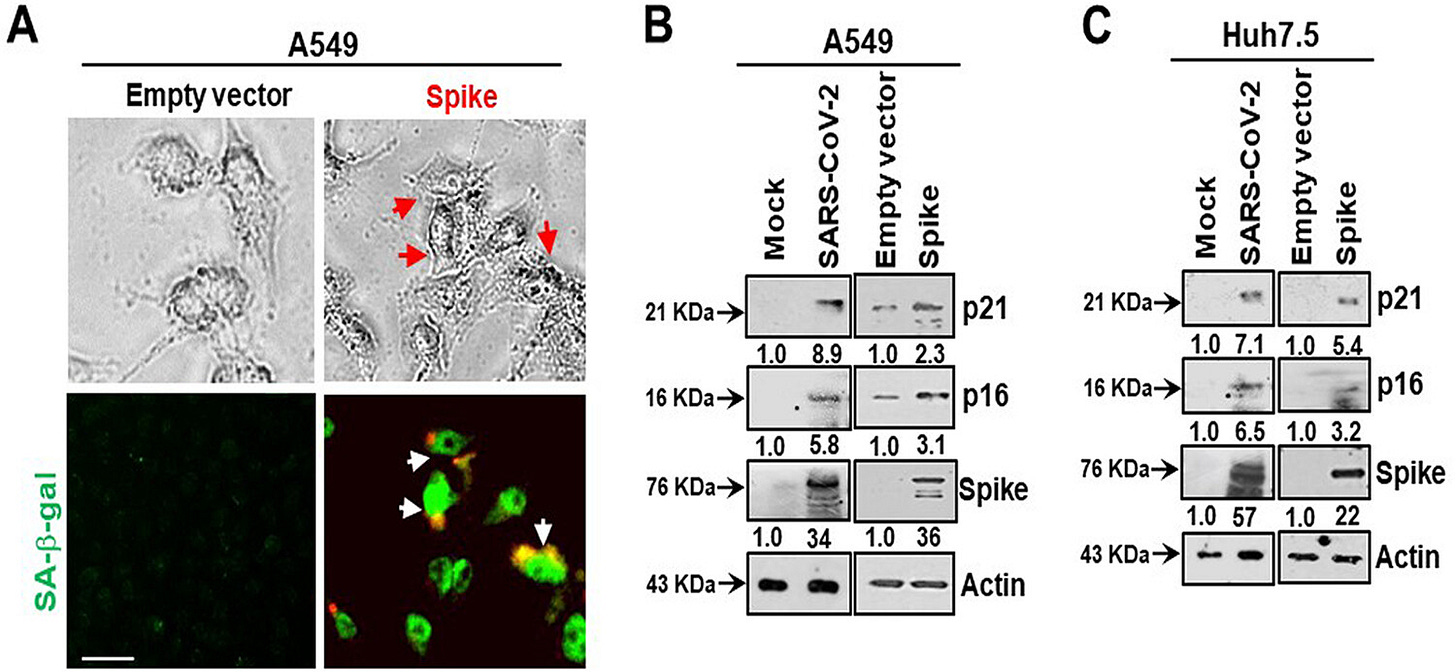

In 2021, Meyer et al conducted an in vitro study using spike protein transfected A549 cells: “SARS-CoV-2 Spike Protein Induces Paracrine Senescence and Leukocyte Adhesion in Endothelial Cells”2.

Increased mortality in COVID-19 cases is often associated with microvascular complications. We have recently shown that severe acute respiratory syndrome coronavirus 2 (SARS-CoV-2) spike protein promotes an inflammatory cytokine interleukin 6 (IL-6)/IL-6R-induced trans signaling response and alarmin secretion. Virus-infected or spike-transfected human epithelial cells exhibited an increase in senescence, with a release of senescence-associated secretory phenotype (SASP)-related inflammatory molecules.

A BRD4 inhibitor reverses the senescent effects of spike on epithelial cells:

Introduction of the bromodomain-containing protein 4 (BRD4) inhibitor AZD5153 to senescent epithelial cells reversed this effect and reduced SASP-related inflammatory molecule release in TMNK-1 or EAhy926 (representative human endothelial cell lines), when cells were exposed to cell culture medium (CM) derived from A549 cells expressing SARS-CoV-2 spike protein. Cells also exhibited a senescence phenotype with enhanced p16, p21, and senescence-associated β-galactosidase (SA-β-Gal) expression and triggered SASP pathways.

Here, we measured intracellular ROS and observed an approximately 3-fold increase in ROS in A549 spike-transfected cells compared to levels in empty plasmid-transfected control cells (Fig. 2A). Increased production of intracellular ROS contributes to DNA damage, leading to cellular senescence. We observed an increase in the DNA damage response marker γ-H2AX in cells transfected with the viral spike gene (Fig. 2B). γ-H2AX was found to be localized to the nucleus in viral spike-transfected A549 cells (Fig. 2C). Our results indicated that SARS-CoV-2 spike protein expression induces a senescent state in spike-transfected A549 cells that is associated with the DNA damage response and increased ROS generation.

Bromodomain-containing protein 4 (BRD4) is a novel regulator of the senescence mechanism. BRD4 expression is required in senescence immune surveillance and SASP-associated signaling (15). Spike gene transfection of A549 cells led to an enhanced expression of BRD4 (Fig. 3A). A549 cells were transfected with the SARS-CoV-2 spike protein and incubated for 48 h prior to exposure for 16 h to the BRD4 inhibitor AZD5153. Spike protein expression induced p21 and p16 senescence markers, the levels of which were reduced by the addition of AZD5153 (Fig. 3B). Spike-transfected A549 cells exhibited enhanced secretion of SASP-related inflammatory molecules like the alarmin HMGB1 and cytokines interleukin 1α (IL-1α) and IL-6.

Senescent cells secrete inflammatory molecules that may induce paracrine senescence in their surrounding cells. We examined whether senescent epithelial cells generated by spike transfection stimulate paracrine senescence in nearby endothelial cells where SARS-CoV-2 spike protein expression is absent. For this, we incubated endothelial TMNK-1 cells with conditioned culture medium (CM) collected from SARS-CoV-2 spike-expressing A549 cells. We observed green fluorescence associated with SA-β-Gal expression in spike CM-treated cells (Fig. 4A). We also observed a strong expression of the senescence markers p21 and p16 from spike CM-treated TMNK-1 cells.